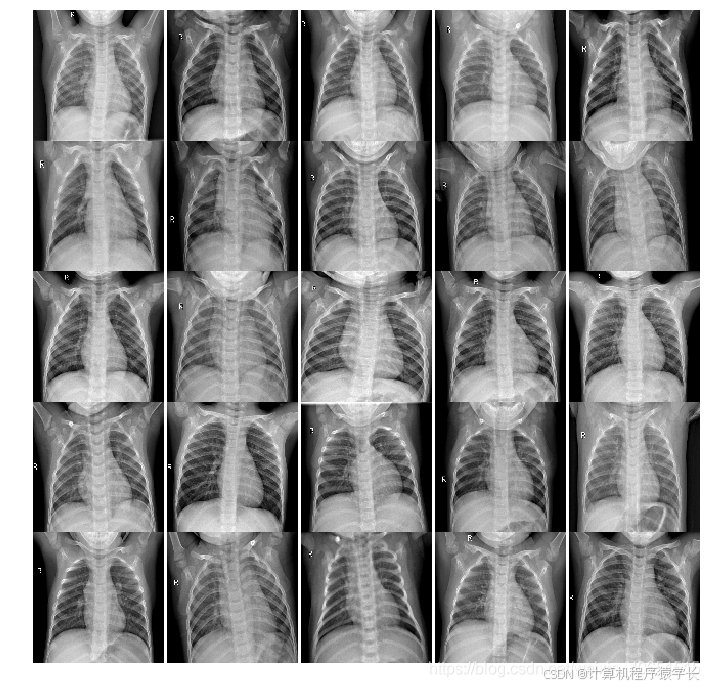

本文主要基于kaggle数据集(胸部X射线照片)进行肺炎疾病的识别与预测。主要将探索两部分内容:

一是:通过训练深度学习模型(多层CNN模型),使CNN能够根据患者胸部的X射线图像检测患者是否患有肺炎疾病。